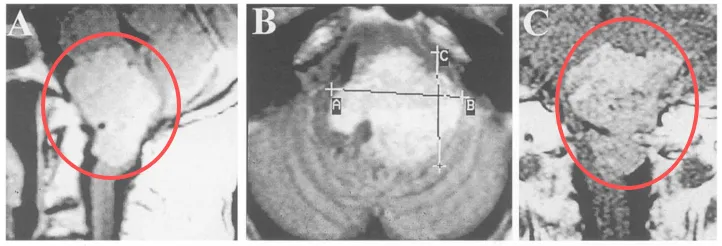

术前MRI

MR是目前确诊枕骨大孔区脑膜瘤重要的手段,T1加权多呈等信号或略低信号,T2加权为等信号或高信号,部分可见囊变坏死、出血,肿瘤边界大多较清晰,通过静脉给予钆造影剂增强扫描后肿瘤显著均匀强化,大部分可出现典型的“脑膜尾”征。

同时MRI矢状位和冠状位的影像学图像可直接显示延髓、颈髓的受压情况,肿瘤侵犯脑干的软脑膜时,T2加权像出现脑干区域的高信号改变,FLAIR像更加明显,这往往提示脑干水肿的表现,往往肿瘤压迫脑干导致脑干水肿影响肿瘤切除程度及术后并发症。增强结果可提示肿瘤的血供丰富情况,同时在轴位及冠状位上也有助于判断肿瘤与同侧椎动脉及周边硬脑膜之间的关系。MRI也是将枕骨大孔区肿瘤与颈椎病、寰枕畸形等进行鉴别的重要手段。

图:典型的枕骨大孔腹侧的脑膜瘤,伴有沿斜坡走行的鼠尾征(上图),肿瘤常侵及颈静脉孔使手术更加困难,远外侧入路切除肿瘤。

图:枕骨大孔脑膜瘤并脑干水肿提示软脑膜被侵及,提示采用次全切除来保护神经功能。